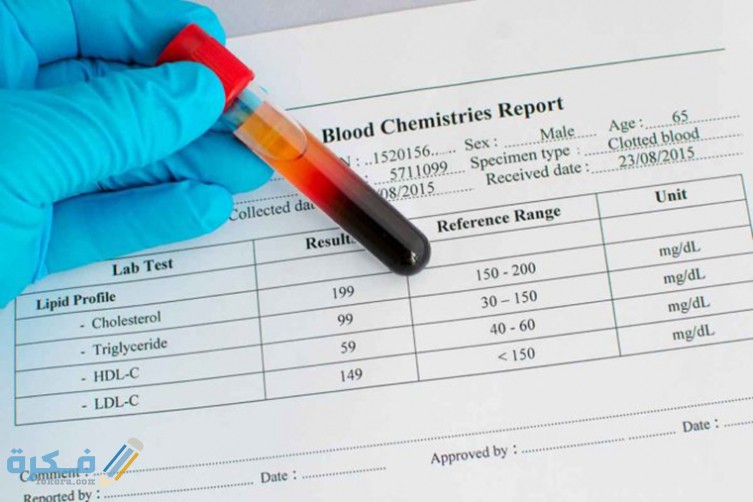

أكمل القراءة »ما هو ال P-LCC في تحليل الدم عبر موقع فكرة، يتسائل العديد من الأشخاص عن تحليل P-LCC، وسوف نقدم لكم…

أكمل القراءة »كيف أعرف إني شفيت من مقاومة الإنسولين عبر موقع فكرة ، الإنسولين هو إحدى أعظم الاكتشافات في العصر الحديث، حيث انه…

أكمل القراءة »كم عدد لترات الدم في جسم الإنسان عبر موقع فكرة، الدم هو تقريبًا اهم سائل في جسم الانسان وحدوث اي…